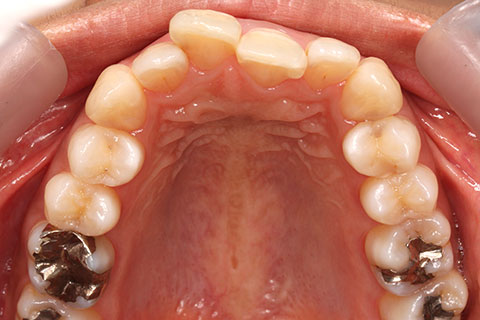

ハーフリンガル矯正3:上の歯のみ舌側矯正で治療(矯正期間24ヶ月)

治療前

治療中(開始直後)

治療中(開始半年後)

治療後

- 年齢・性別

- 25歳女性

- 治療期間

- 2年0ヶ月

- 抜歯

- 上下4番抜歯

- 治療費

- 110万円

- 治療内容

- 施術の副作用(リスク)

- 表側矯正と比較して、力学的な操作性が複雑なため、ボーイングエフェクトを起こしやすい。